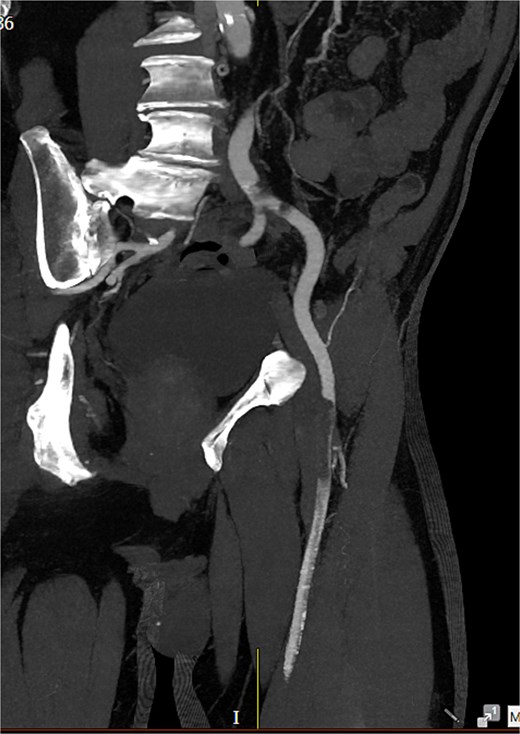

Computed tomography (CT) angiography (Figs 1 and 2) revealed a near-occlusive filling defect at the left common iliac bifurcation. Further embolic material extended into the left common femoral bifurcation, profunda femoris, and superficial femoral artery. An embolic occlusion was also present in the below-knee popliteal artery, extending to the trifurcation, with partial reconstitution of the calf vessels. Emboli were seen in the posterior tibial and peroneal arteries. On the right side, embolic material was noted in the distal profunda and popliteal artery, with further emboli in the tibio-peroneal trunk. The patient underwent bilateral femoral thromboembolectomy.

A near-occlusive filling defect at the left common iliac bifurcation. Further embolic material extended into the left common femoral bifurcation, profunda femoris, and superficial femoral artery.